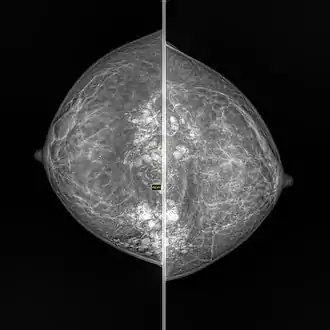

Silicone granuloma